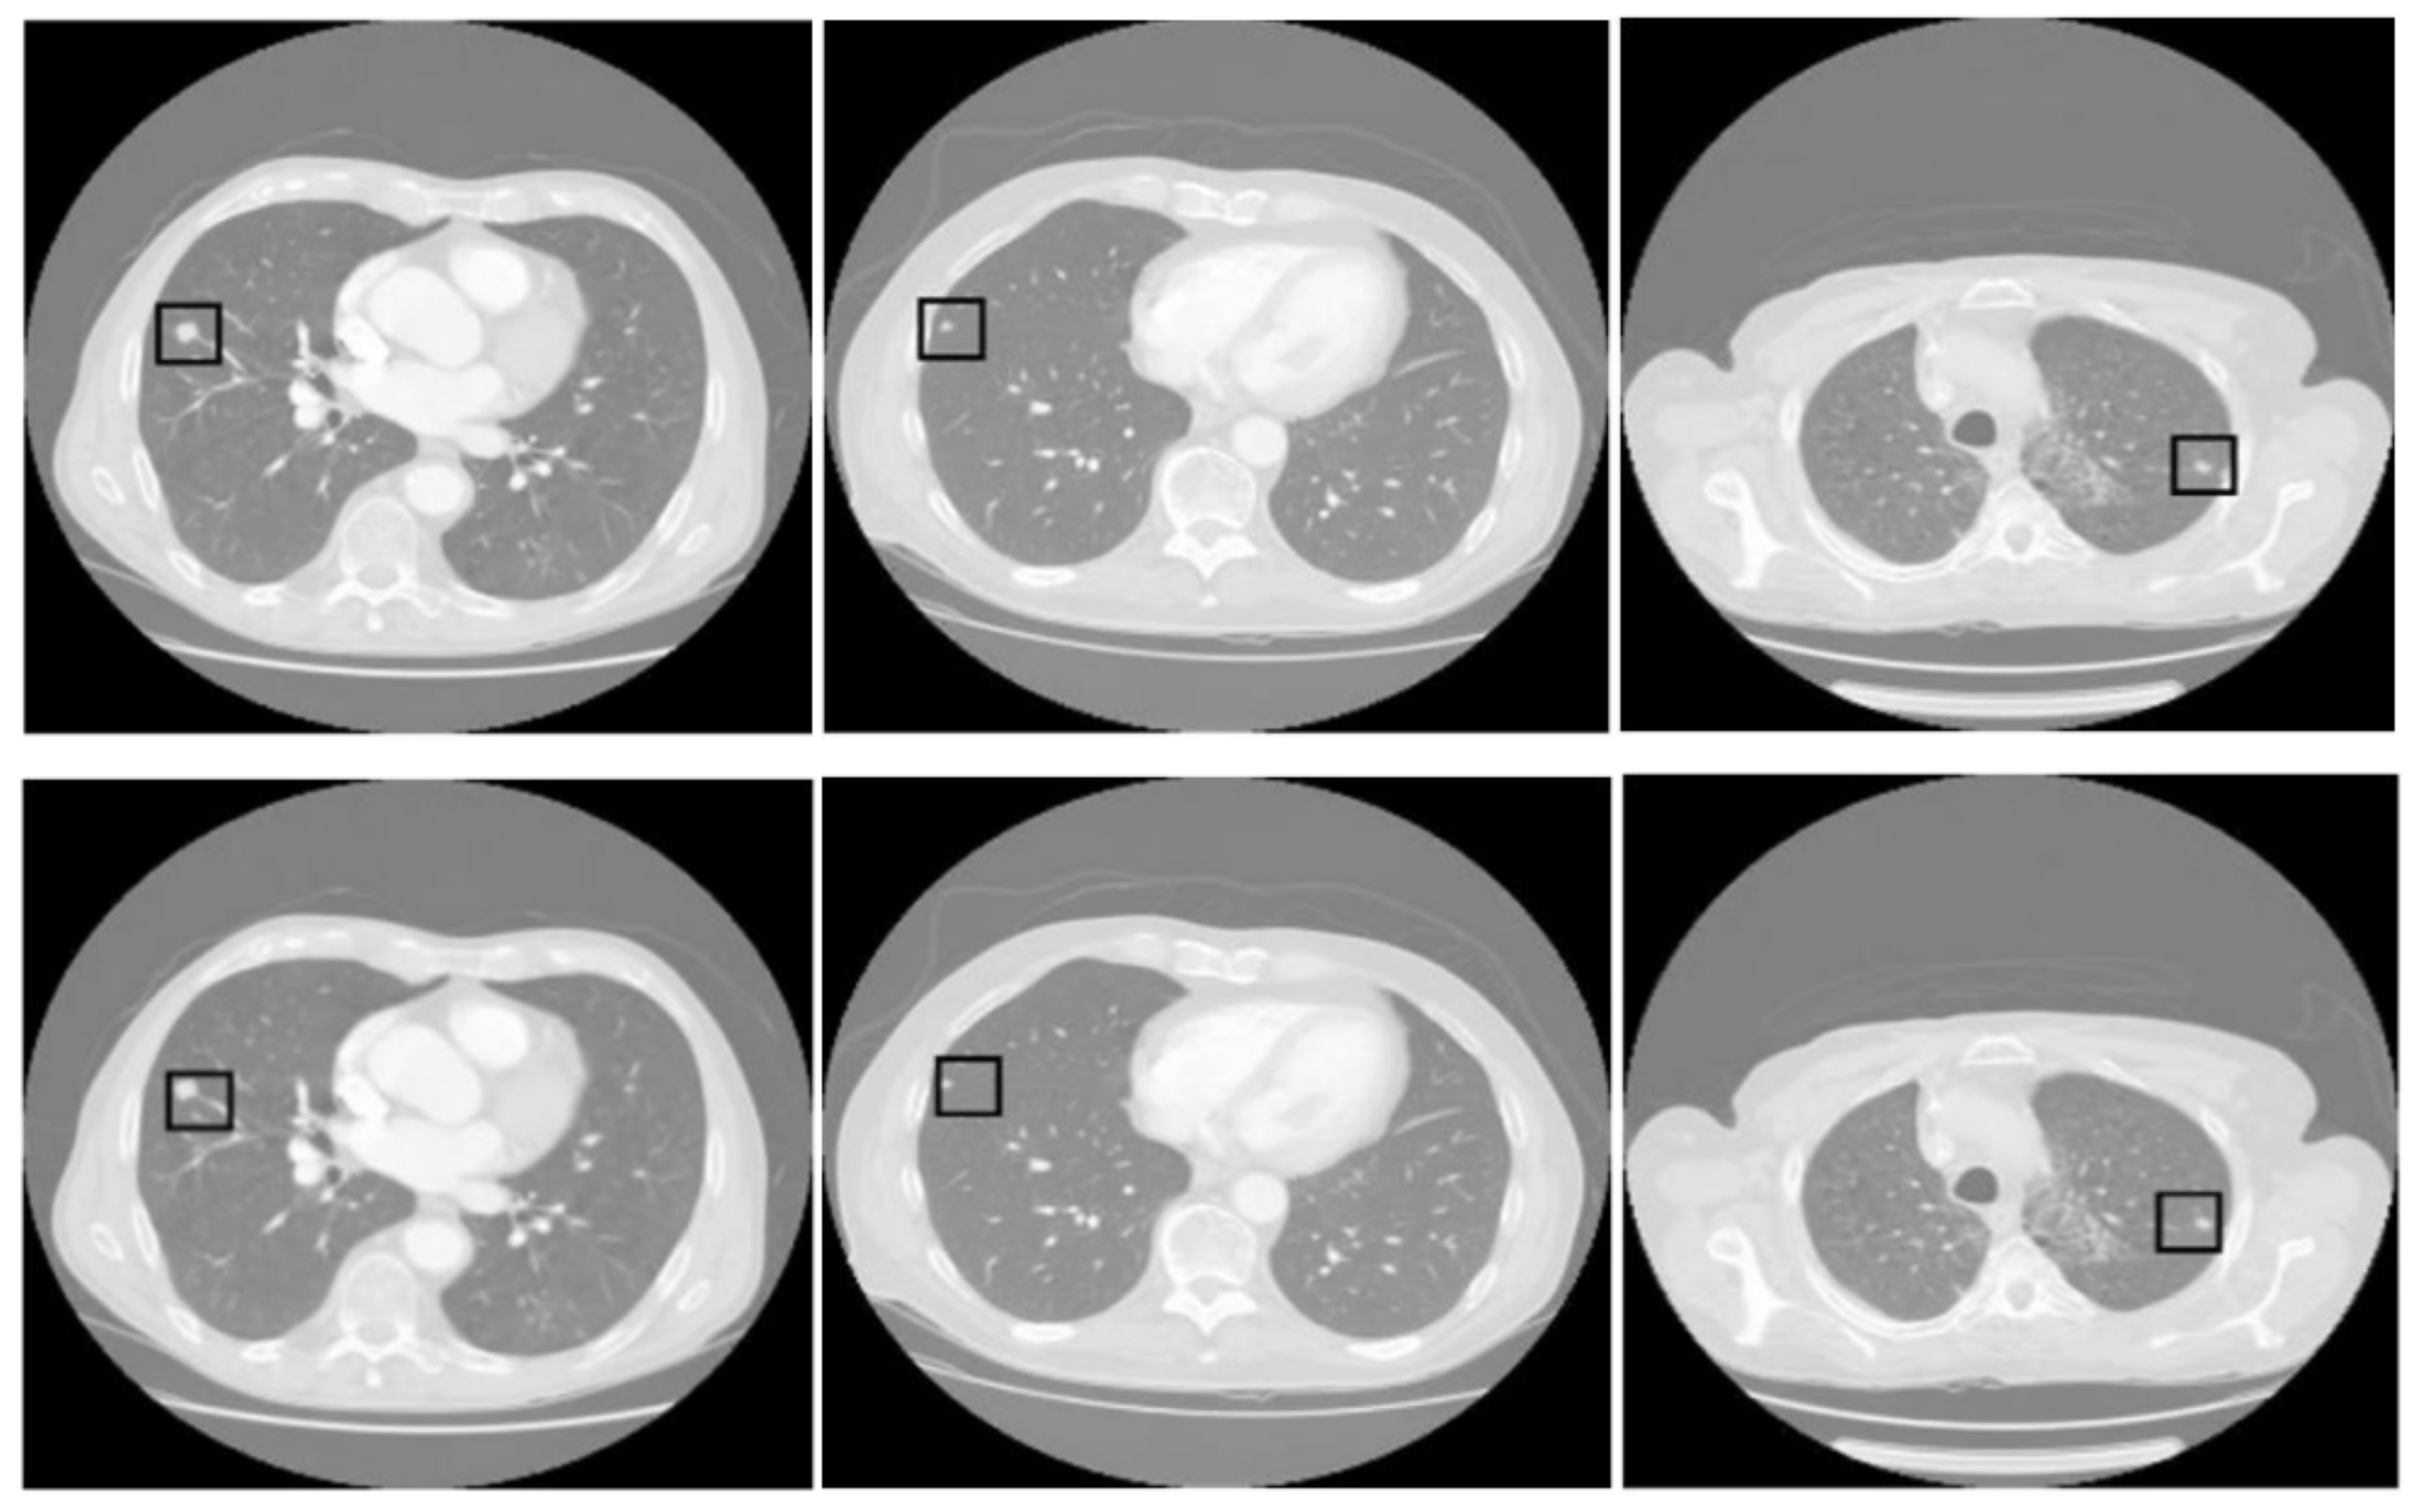

Figure 3 displays three sets of images produced by the proposed lung segmentation model. The top row illustrates the original CT scans from patients, depicting cross-sectional images of the thoracic cavity. These scans provide a clear view of the lung structures, bones, and surrounding tissues, with radiodensity variations allowing these components’ differentiation. In the corresponding images of the bottom row, the results of the segmentation model are evident. Here, the lung regions have been delineated and filled in, starkly contrasting with the non-lung areas, which appear as black space. The segmentation model seems to have successfully extracted the lung regions from the CT images with high accuracy. In the first column, the model accurately identifies the lung boundaries and the separation between the left and right lungs. The second column shows a similarly precise segmentation, with the model correctly excluding the heart and the spine, which are centrally located in the thoracic cavity. In the third column, despite the more complex lung structures due to either a pathological condition or a scanning artifact, the model has managed to delineate the lung region, preserving the intricate details and the shape of the lungs.

Figure 5 presents three pairs of images generated by the proposed tumor detection model, where the ground truth annotations are displayed in the top row, and the outputs of the model are shown in the bottom row. A collective analysis of these images suggests that the proposed model demonstrates a commendable level of precision in pinpointing the location of lung tumors. Across the set, the regions marked by the model align well with the ground truth indicators, denoted by squares. This alignment indicates that the model has successfully learned to identify the critical features of lung tumors from CT scans and can consistently distinguish tumor tissue from surrounding anatomical features.